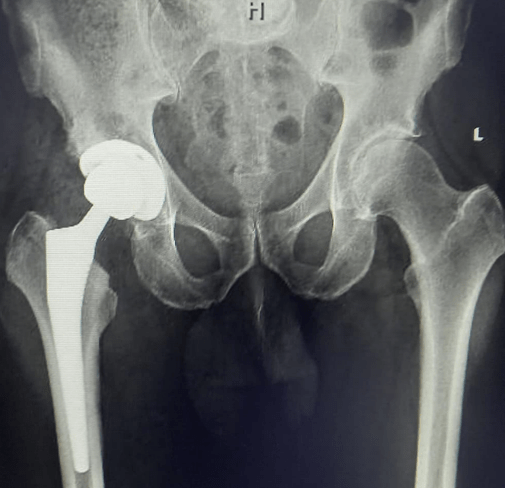

Total hip replacement is a surgical procedure that involves removing damaged or diseased parts of the hip joint and replacing them with artificial components. Dr Paul Macnamara is one of the busiest hip replacement surgeons in Dubai, and regularly sought by both domestic and international patients.

During the surgery Dr Paul will remove the damaged portions of the joint, including the head of the femur and the socket of the hip bone, and replace them with metal or ceramic components that are secured to the bones.